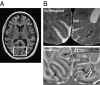

Recent advances in high-field MRI have dramatically improved the visualization of human brain anatomy in vivo. Most notably, in cortical gray matter, strong contrast variations have been observed that appear to reflect the local laminar architecture. This contrast has been attributed to subtle variations in the magnetic properties of brain tissue, possibly reflecting varying iron and myelin content. To establish the origin of this contrast, MRI data from postmortem brain samples were compared with electron microscopy and histological staining for iron and myelin. The results show that iron is distributed over laminae in a pattern that is suggestive of each region's myeloarchitecture and forms the dominant source of the observed MRI contrast.